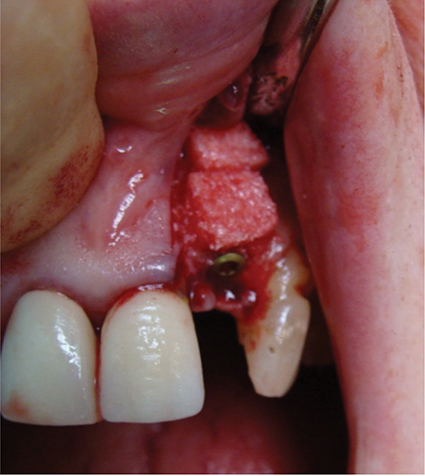

Above: A case of peri-implantitis requiring debridement and bone grafting.